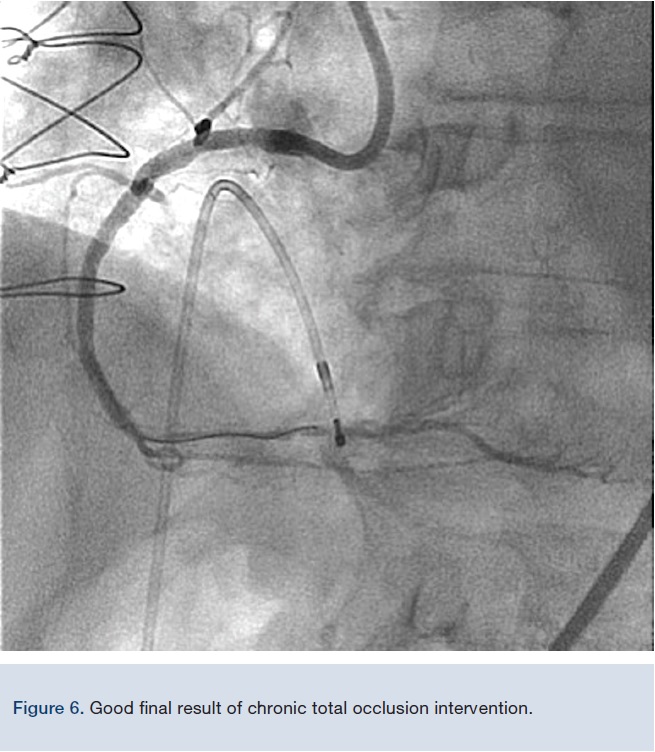

An 81-year-old female continued to experience effort angina with activities of daily living in spite of optimal medical therapy. She had a PCI of her left anterior descending artery (LAD) and obtuse marginal branch (OM) 7 years prior. Medications included aspirin, metoprolol, amlodipine, rosuvastatin, furosemide, and sublingual nitroglycerine. Cardiovascular examination was unremarkable except for a grade 2/6 systolic murmur at the left sternal border, radiating to the carotid arteries. Electrocardiogram (EKG) showed sinus rhythm with first-degree atrioventricular block. An echocardiogram revealed preserved left ventricular function with mild aortic stenosis. Coronary angiogram showed patent stents and mild non-obstructive disease in the left system. A large, severely tortuous, fully calcified right coronary artery (RCA) was noted to have a 90% distal stenosis followed by a 70% lesion (Figure 3).

Given the tortuosity and calcification, very good catheter support was needed for PCI. An 8 French (Fr), 45 cm sheath was inserted into the femoral artery and an 8 Fr multipurpose guide catheter was chosen. After deep intubation of the RCA with the guide catheter, a Balance Middleweight guide wire (BMW) (Medtronic) was used to cross the lesion; however, just as the BMW crossed, the guide catheter prolapsed back into the aorta. At this point, an 8 Fr GuideLiner was inserted into the guide catheter with a 5.5 Fr GuideLiner inserted into it (outside the patient) over a BMW (Figures 1-2). This system was advanced into the RCA with the guide catheter deeply seated. The 8 Fr GuideLiner tip was advanced to the mid RCA and the 5.5 Fr GuideLiner tip reached mid vessel. With this support system, both stenoses were predilated with a 2.5 x 15 mm non-compliant balloon. First, a 3.5 x 12 mm Xience stent (Abbott Vascular) was placed in the distal coronary lesion, which required pushing of the 5.5 Fr GuideLiner further into the distal vessel, past the first lesion (Figure 4). Next, a 4.0 x 28 mm Xience stent was advanced to the distal tip of the 5.5 Fr GuideLiner and it was “de-sheathed” by pulling the GuideLiner back. With a good final result, the patient was discharged home the following day in good condition and remained angina free.